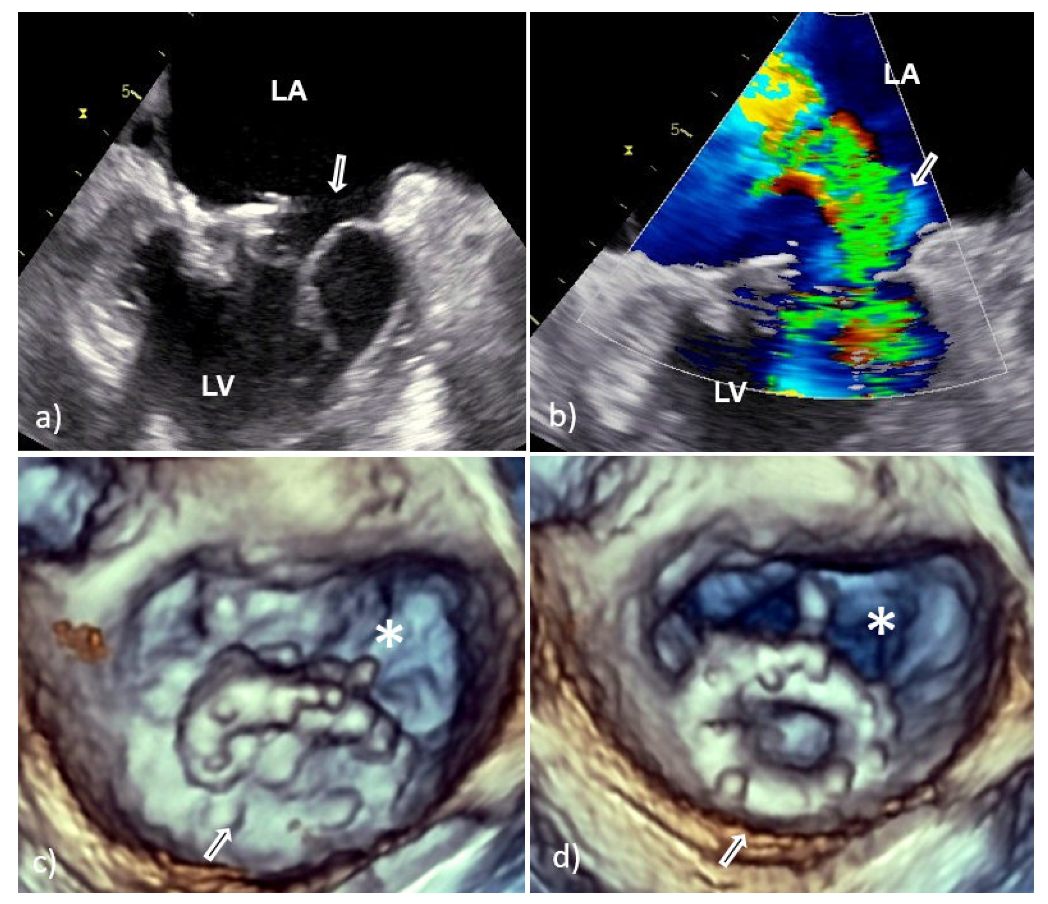

However, vegetative growth can occur as thickening and irregularity of the normally smooth contour of the suture ring (Figure 2) or in the case of biological PVE as vegetation attached to the leaflets (Figure 3), sometimes with their consequent perforation or creation of a pseudoaneurysm [6,7].

Because the risk of embolism in patients with IE is related to the size, morphology, and mobility of vegetation, proper assessment of vegetation and monitoring of their size during antibiotic therapy have important prognostic implications [10,11]. Therefore, the accuracy and reproducibility of vegetation measurements is particularly important due to the greater effectiveness of early surgical interventions in patients with large mobile vegetation [10,11]. In this context, it is important that 2D TEE could underestimate vegetation compared to 3D TEE primarily due to limitations in selecting the maximum true diameter of irregular masses [10,11]. This shortcoming is solved by 3D TEE which allows infinite planes and volumetric reconstruction of masses (Figure 2). Because the main diameter of vegetation is important in the assessment of medical treatment response, as well as for setting a surgical indication in patients without other surgical indications, differences between the two TEE techniques in accuracy of vegetation measurements may have key therapeutic implications. In addition, 3D TEE allows better morphological classification of vegetation (e.g., filiform, sedentary, and clustered), and recognition of those associated with fragility and embolization (it seems that sedentary vegetation has the least embolic potential) [10,11]. Therefore, the main advancement of 3D TEE over 2D TEE is better assessment of vegetation characteristics—size, location, number, morphology, consistency, mobility, and relationship to valve structure—resulting in better prediction of potential embolic risk [10,11].

Figure 3. Transesophageal echocardiography of mitral bioprosthesis endocarditis caused by Enterococcus faecalis: 2D TEE (a) and 3D TEE view (b,c) from the atrial side showed a sedentary type of vegetation (white arrow) clinging to the leaflet with a wide base; view from the left ventricle showed good leaflet appearance and coaptation with no possible complications of PVE (d). 2D TEE—two-dimensional transesophageal echocardiography; 3D TEE—three-dimensional transesophageal echocardiography; PVE—prosthetic valve endocarditis; LA—left atrium; and LV—left ventricle.